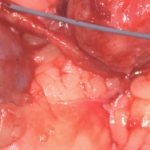

たった1mmの大きさの尿管結石でも猫の尿管を閉塞してしまうことがあります。血液検査、尿検査、超音波検査、無麻酔CT検査などで外科的に対応すべきか?詳しく評価します。閉塞してもすぐには腎盂の拡張はそれほど顕著ではありませんし、片側のみであれば血液検査に異常値が検出されないこともしばしばです。マイクロサージェリーで短尺ステントと尿管新吻合術で対応しました。通常はシュウ酸カルシウムであり溶解できないので非常に厄介です。